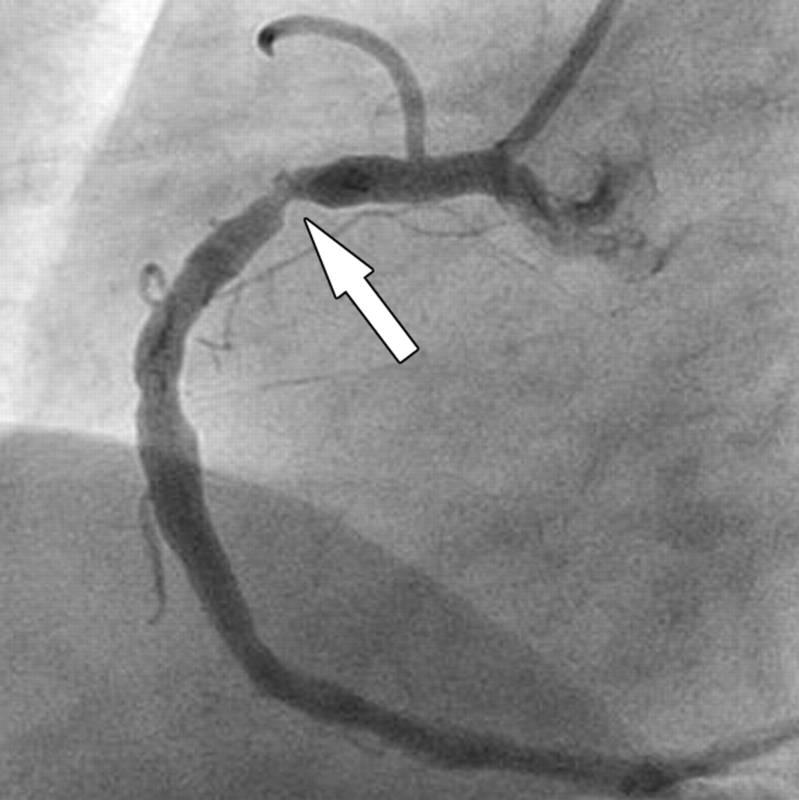

На сегодняшний день существуют различные методы исследования патологий сердечно-сосудистой системы, которые отличаются эффективностью и стоимостью. Сегодня людей больше всего интересует стоимость коронографии сердца в Бакулева, так как эта методика является очень эффективным средством в арсенале современных кардиологов. Она представляет собой рентгенографический метод исследования, который дает возможность детально исследовать коронарную артерию, определить точное место сужения ее просвета атеросклеротической бляшкой, выяснить, какой характер и протяженность носит это сужение, то есть, своевременно диагностировать ишемическую болезнь и своевременно оказать помощь больному. Обычно эта медицинская процедура назначается пациентам, которым в скором времени планируется проведение стентирования или шунтирования. В зависимости от результатов этого исследования и будет определена максимально подходящая операция для конкретного случая и для больного.

Коронография сердца — это важный диагностический метод, который позволяет врачам оценить состояние коронарных артерий и выявить наличие стенозов или других патологий. Специалисты подчеркивают, что данная процедура является ключевой для диагностики ишемической болезни сердца и других сердечно-сосудистых заболеваний. Во время коронографии в сосуды вводится контрастное вещество, что позволяет получить четкие изображения артерий на рентгеновских снимках. Врачи отмечают, что этот метод не только помогает в диагностике, но и может быть использован для планирования дальнейшего лечения, включая ангиопластику или установку стентов. Несмотря на минимальные риски, связанные с процедурой, специалисты рекомендуют ее проводить при наличии показаний, так как своевременная диагностика может существенно улучшить прогноз для пациента.

После того как пластиковая трубка будет установлена в артерии, через нее запускают специальное контрастное вещество, которое растекается плавно по ней. В это время врач тщательно следит за осуществлением процедуры и при помощи рентген аппарата производит соответствующие снимки. Исходя из того, что человек имеет две главнейших артерии, то катетер устанавливается сначала в одну, потом — в другую. Снимки делаются для каждой артерии под различными углами. Затем хирург проводит анализ полученных снимков и выясняет наличие и количество закупорок, а также сужение сосудов и их локализацию. Подробнее узнать о данной методике, а также увидеть ее проведение, можно, просмотрев видео, где показано, как делают коронографию сердца.